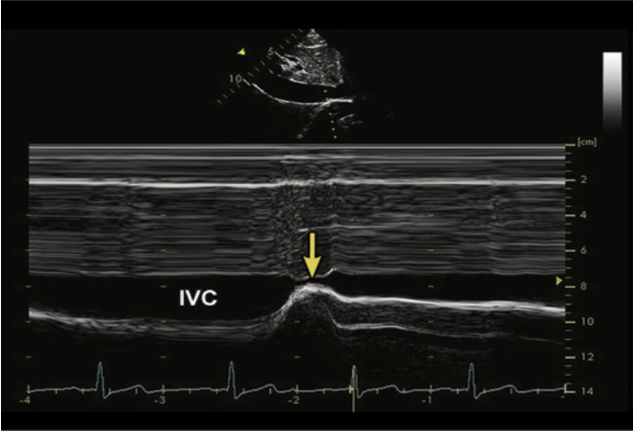

排除高水平PEEP、腹腔高压、慢性右心功能不全、三尖瓣重度关闭不全、急性右心室梗死导致的宽大的IVC宽度的情况,如果IVC<1 cm,基本可以预测有容量反应性;如果IVC>2 cm,基本排除了容量反应性。(2)下腔静脉变异度(dIVC):在机械通气患者中,下腔静脉的直径在吸气时明显扩张(iIVC),在呼气时明显缩短(eIVC),我们定义下腔静脉在吸气时和呼气时的变化为下腔静脉的变异度dIVC,计算公式为:dIVC=(iIVC-eIVC)/eIVC×100%。可以使用M型超声测量IVC的宽度变化来获得该数据。相关测量示意图如图6所示。研究发现,对于机械通气患者,在相对较高的潮气量和相对较低的PEEP下,通过dIVC>18%来预测容量反应性和前负荷的储备情况是非常准确的。

(3)下腔静脉塌陷度(cIVC):对自主呼吸患者而言,我们更多会采用IVC在患者主动呼吸时发生塌陷的程度(cIVC)来评价容量反应性,相关计算公式为:cIVC=(eIVC-iIVC)/eIVC×100%,eIVC代表下腔静脉呼气末直径,iIVC代表下腔静脉吸气末直径。一般来说,参考的cIVC>40%代表有容量反应性。根据美国超声心动图指南推荐,dIVC<2.1 cm伴用力吸气cIVC>50%时,考虑CVP为0~5 mmHg;dIVC>2.1 cm伴用力吸气cIVC<50%时,CVP相当于10~20 mmHg;当dIVC和cIVC不符合前面情况时,可以考虑CVP为5~10 mmHg。(4)颈内静脉(LJV)变异率:患者仰卧位床头抬高至30°,在颈内静脉短轴切面,使用高频线阵探头观察颈内静脉,然后旋转探头至长轴切面,通过观察颈静脉呼吸周期中的塌陷来评估。在机械通气患者,LJV扩张超过18%,或者LJV扩张超过7%合并PPV超过12%,可以定义为有容量反应性。(5)左室流出道速度-时间积分(VTI)或心排量(CO):在心尖五腔心切面,对主动脉-左室流出道采用PW模式,描记患者的血流频谱,可以获得每次搏动下速度-时间的积分(VTI)(图7),每搏量(SV)=VTI×π×(左室流出道直径/2)2,心排量CO=SV×HR。在进行被动抬腿试验(PLR)的患者中,若PLR前后,VTI或SV或CO增加比例超过12%,患者排除使用弹力袜、严重低血容量、腹肌紧张、腹腔高压后,则证明患者存在容量反应性。